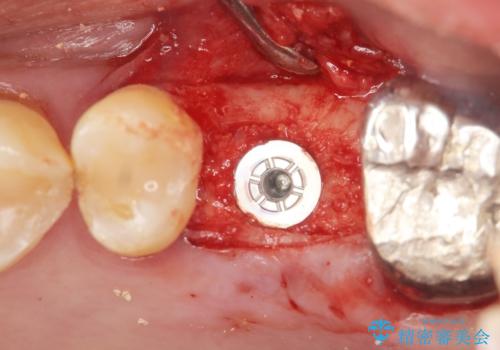

精査したところ上顎骨の厚みが薄かったため、ソケットリフト(上顎洞底挙上術)を併用してインプラント治療を行いました。

インプラントの種類:スプライン ツイスト (保証期間:5年)